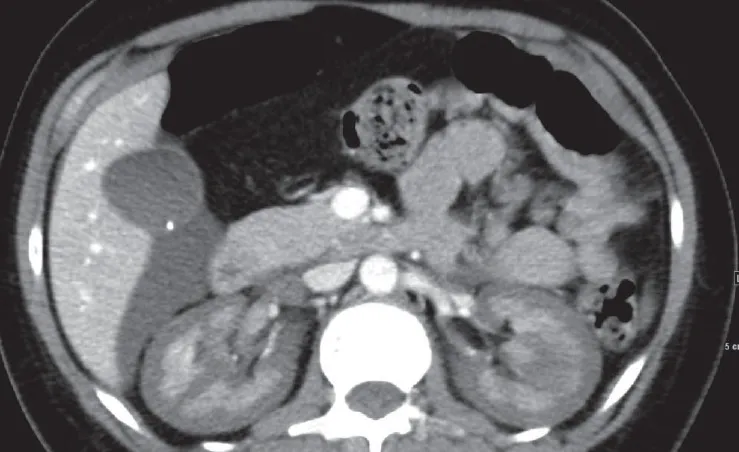

Nos dias seguintes, a creatinina sérica aumentou para 13 mg/dl, acompanhada de anúria. Realizado tomografia computadorizada de abdome (imagem da capa do post) que revelou sinais de necrose cortical renal (NCR), sinais de reversão renal (córtex hipodenso quando comparado a medula renal) com presença de um trombo na veia cava inferior e na veia gonadal direita. A paciente iniciou hemodiálise devido aos sintomas urêmicos e permaneceu dependente da diálise por cerca de dois meses. Após seis meses, a creatinina sérica caiu para 2,4 mg/dl, com um clearance de creatinina de 33 ml/min e proteinúria subnefrótica de 300 mg/d. A paciente continuo em tratamento conservador com diuréticos de alça em baixa dose e anticoagulação.

A NCR é uma forma grave e frequentemente irreversível de lesão renal isquêmica, resultante de uma redução prolongada da perfusão arterial renal. Esta condição é geralmente associada à CIVD e apresenta-se com início abrupto de oligúria ou anúria, algumas vezes acompanhada de hematúria macroscópica e dor no flanco. A TC com contraste mostrou a preservação da medula renal e a hipocaptação cortical (rim reverso), confirmando o diagnóstico de NCR.